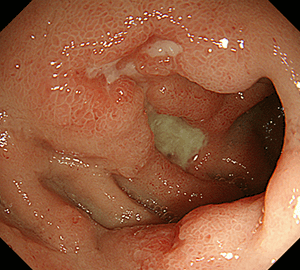

胃潰瘍胃潰瘍